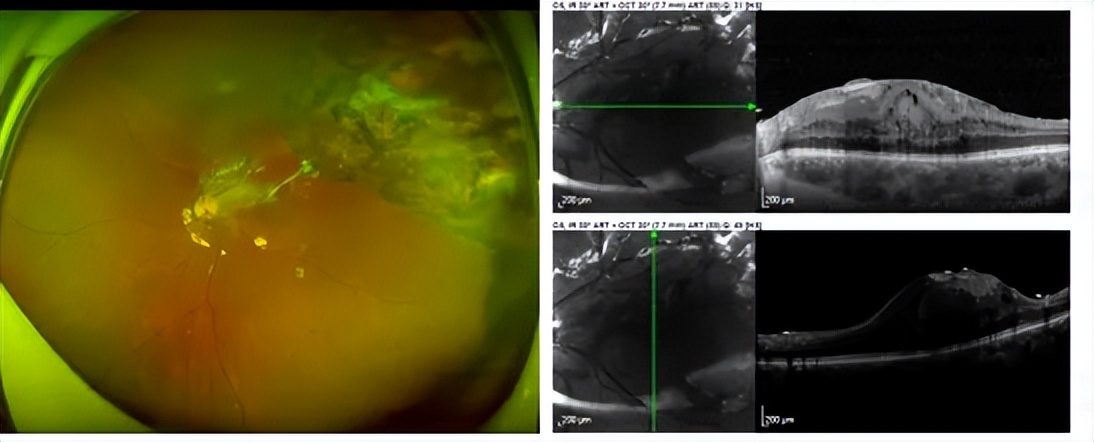

图1. 球内异物取出后,硅油填充眼,黄斑前膜伴增殖膜牵拉,裸眼视力0.02。